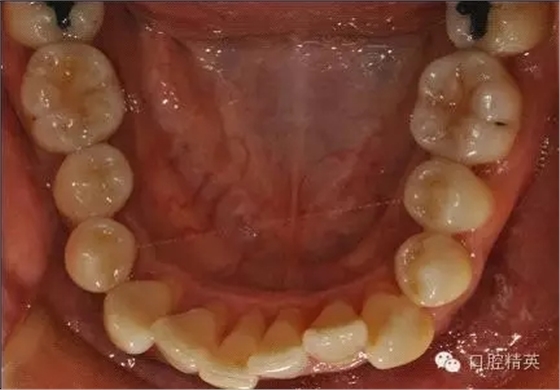

本病例 :女 34歲,主訴刷牙出血,覺牙齒輕度松動一年。

檢查見大量齦上及齦下結(jié)石,探診出血,牙周袋較深,32-42 II度松動。X線片顯示牙槽骨水平吸收。

診斷:成人慢性廣泛性中度牙周炎。

治療前: